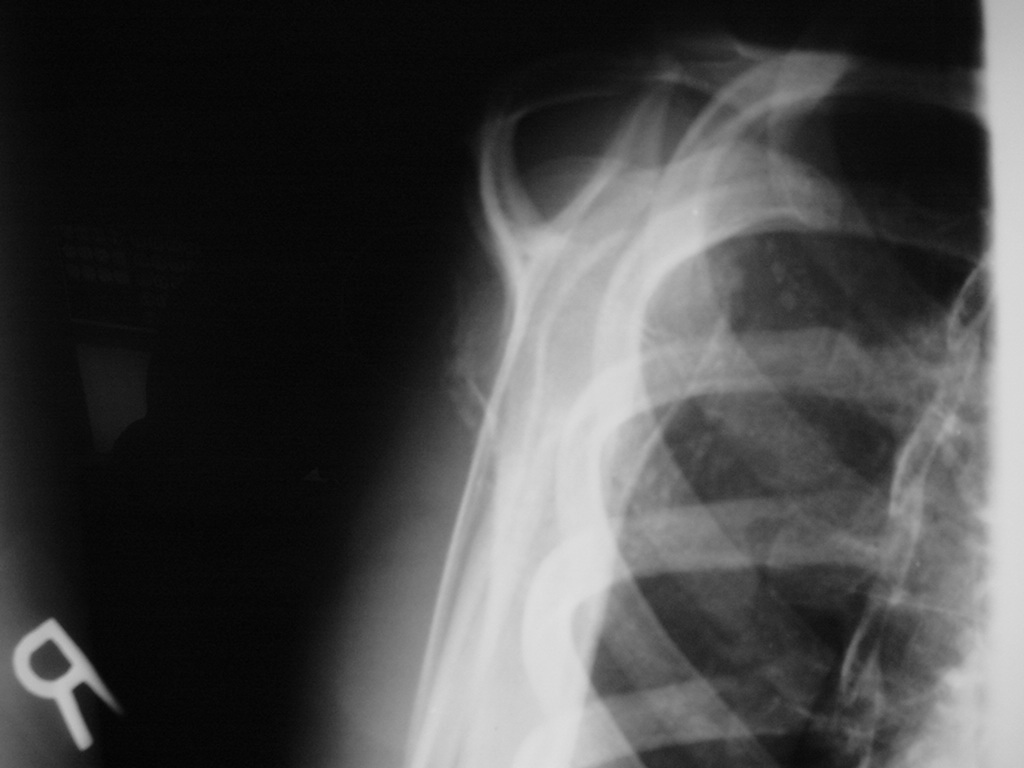

Synovial chondromatosis is an uncommon, benign, process that occurs in large joints, such as the knee (50%), hip, elbow, or shoulder. This process mainly affects synovium and hence most commonly arises from joints and tendons which are lined by synovium. Synovial Chondromatosis may also affect bursae and extend into surrounding soft tissues. This condition is seen in patients between 20 and 50 years of age and most commonly in men (male-female ratio of 2-4/1). The patient usually complains of pain, stiffness, crepitance, swelling, and joint locking. The knee is the most common site to be affected. Symptoms are long-standing and progressive. The plain x-ray may be normal (5 to 33%) or there may be small flecks of calcification (Fig. 1 & 2). On MRI the nodules of cartilage are easily seen. MR imaging may also show synovial thickening, joint erosions and intraarticular calcifications. The signal characteristics of these intraarticular bodies depend of their composition. If mineralization is not present the signal intensity follows the cartilage signal with intermediate signal on T1 images and high signal on T2 weighted MR images. Uniformly calcified bodies follows bone density on all sequences with bone marrow signal centrally and low signal peripherally (Fig. 3-5). Histologically the cartilage is arranged in nodules, which are quite cellular (Fig. 7-9). Synovial lining is present surrounding the cartilage nodules (Fig. 8). The cartilage nodules are often referred to as loose bodies however they are not really loose and embedded in the synovium lining. This is considered a metaplastic condition as opposed to a true neoplastic condition. Rarely it may turn into a malignancy usually a low grade chondrosarcoma. Malignant change is suggested by deep erosions into adjacent bone.